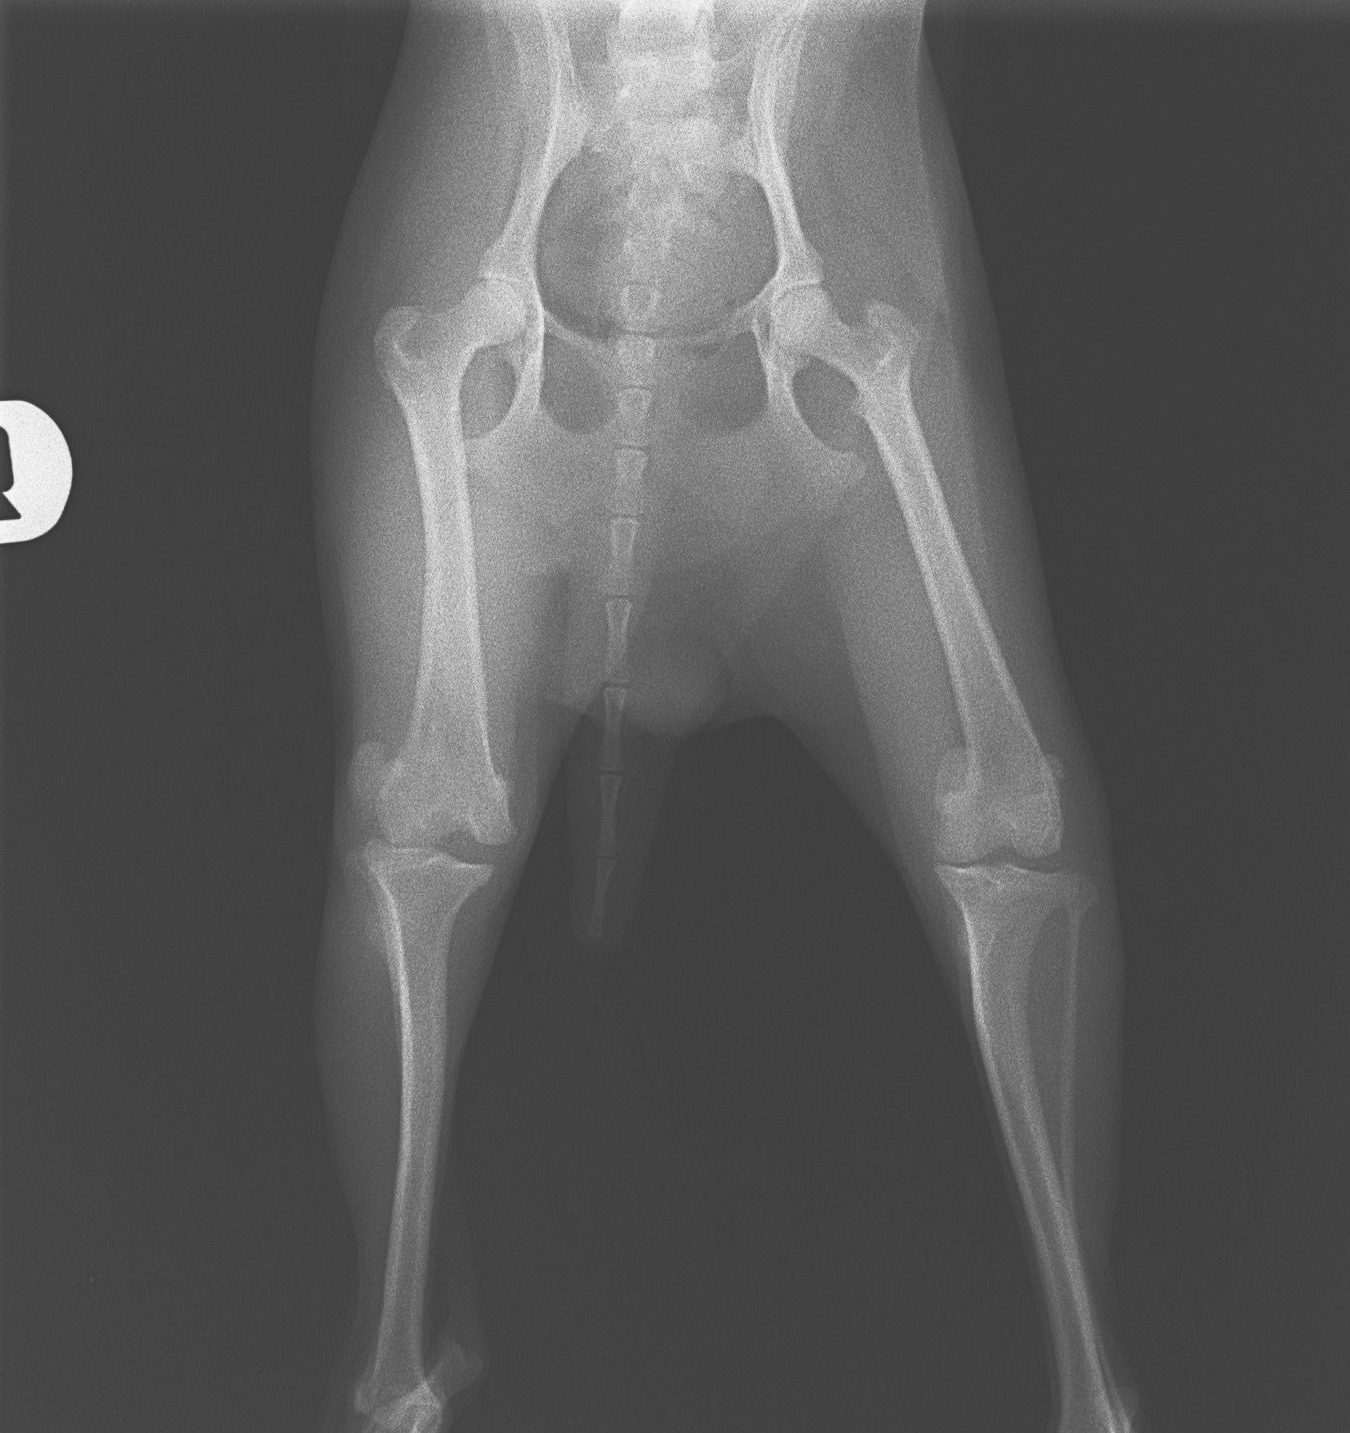

膝蓋骨外方脱臼 トイプードル 1歳齢 雌

レントゲン検査

手術前

右膝蓋骨の外方脱臼、膝関節腔の傾斜が認められる。

手術後

膝蓋骨は正常位に収まり、関節腔の傾斜も認められない。